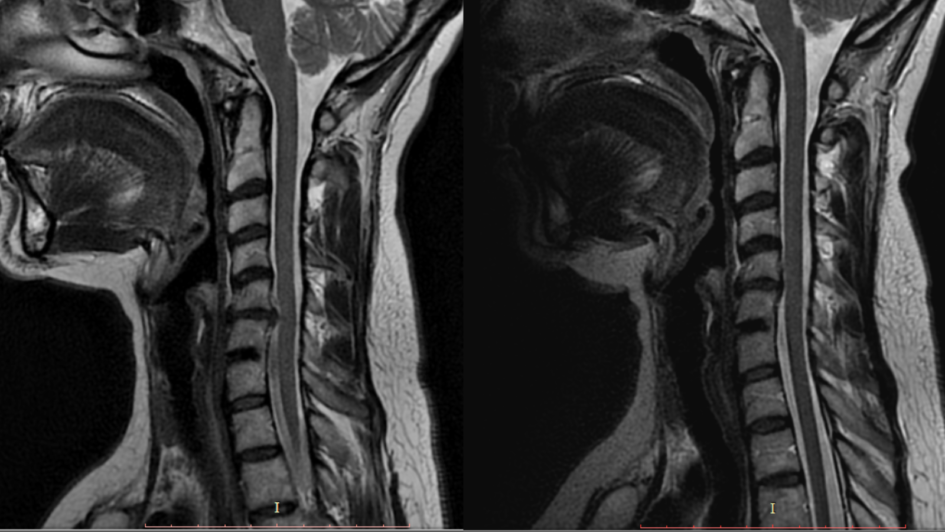

Pacjentka od kilku miesięcy zmagała się z narastającym bólem odcinka szyjnego, który promieniował do kończyny górnej i powodował drętwienie palców. Rezonans magnetyczny potwierdził dyskopatię C5/C6 z modelowaniem rdzenia i foraminostenoza po stronie lewej. W wywiadzie pacjentka podkreślała zmęczenie bólem oraz ograniczenia w codziennym funkcjonowaniu. Lekarz wskazał możliwość leczenia operacyjnego, ale równocześnie zalecił rozpoczęcie rehabilitacji i unikanie przeciążeń.

22.08.2025 – Ostatnia wizyta kontrolna u neurochirurga dr n. med. i n. o zdr. Tomasa Nytra Podczas ostatniej wizyty w sierpniu przeprowadzono kontrolny rezonans. Wynik badania okazał się wyjątkowo korzystny – stwierdzono regresję zmian, a pacjentka dzięki dobrej odpowiedzi organizmu na fizjoterapię po konsultacji z doktorem zdecydowała się zrezygnować z planowanego zabiegu operacyjnego. W codziennym życiu odczuwa już niewiele objawów bólowych, a ewentualne dolegliwości pojawiają się jedynie po dużym przeciążeniu fizycznym lub psychicznym.